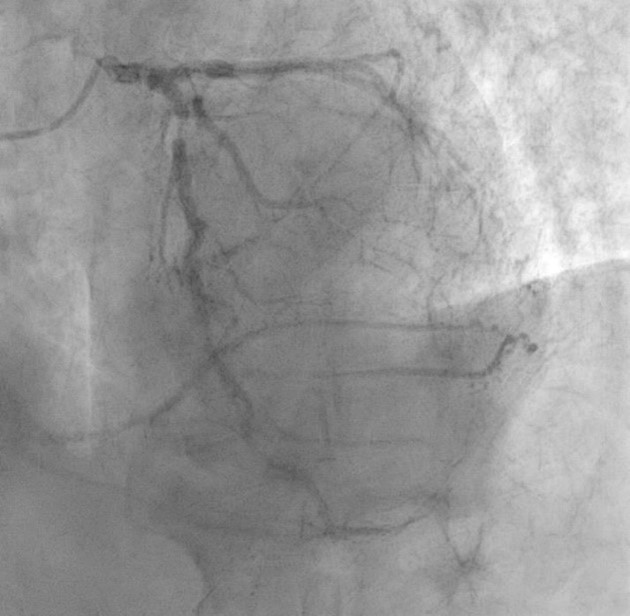

Examination: ultrasound - hypervascular tumor of the right kidney, tumor thrombus in the renal and inferior vena cava (Mayo III) (Fig. 1); MSCT - tumor of the right kidney, tumor thrombus in the inferior vena cava (Fig. 2); coronary angiography - critical stenosis of the coronary arteries (stenosis of the anterior interventricular branch (AIB) in the middle third up to 85-90%) (Fig. 3).

Figure 3: Coronarogram, LAD stenosis in the middle third up to 85-90% (arrow)

Based on the results of the medical consultation, it was decided to perform aorto- and mammary-coronary bypass grafting at the first stage (Fig. 4) and right nephrectomy with inferior vena cava thrombectomy from at the second stage (Figure. 5).